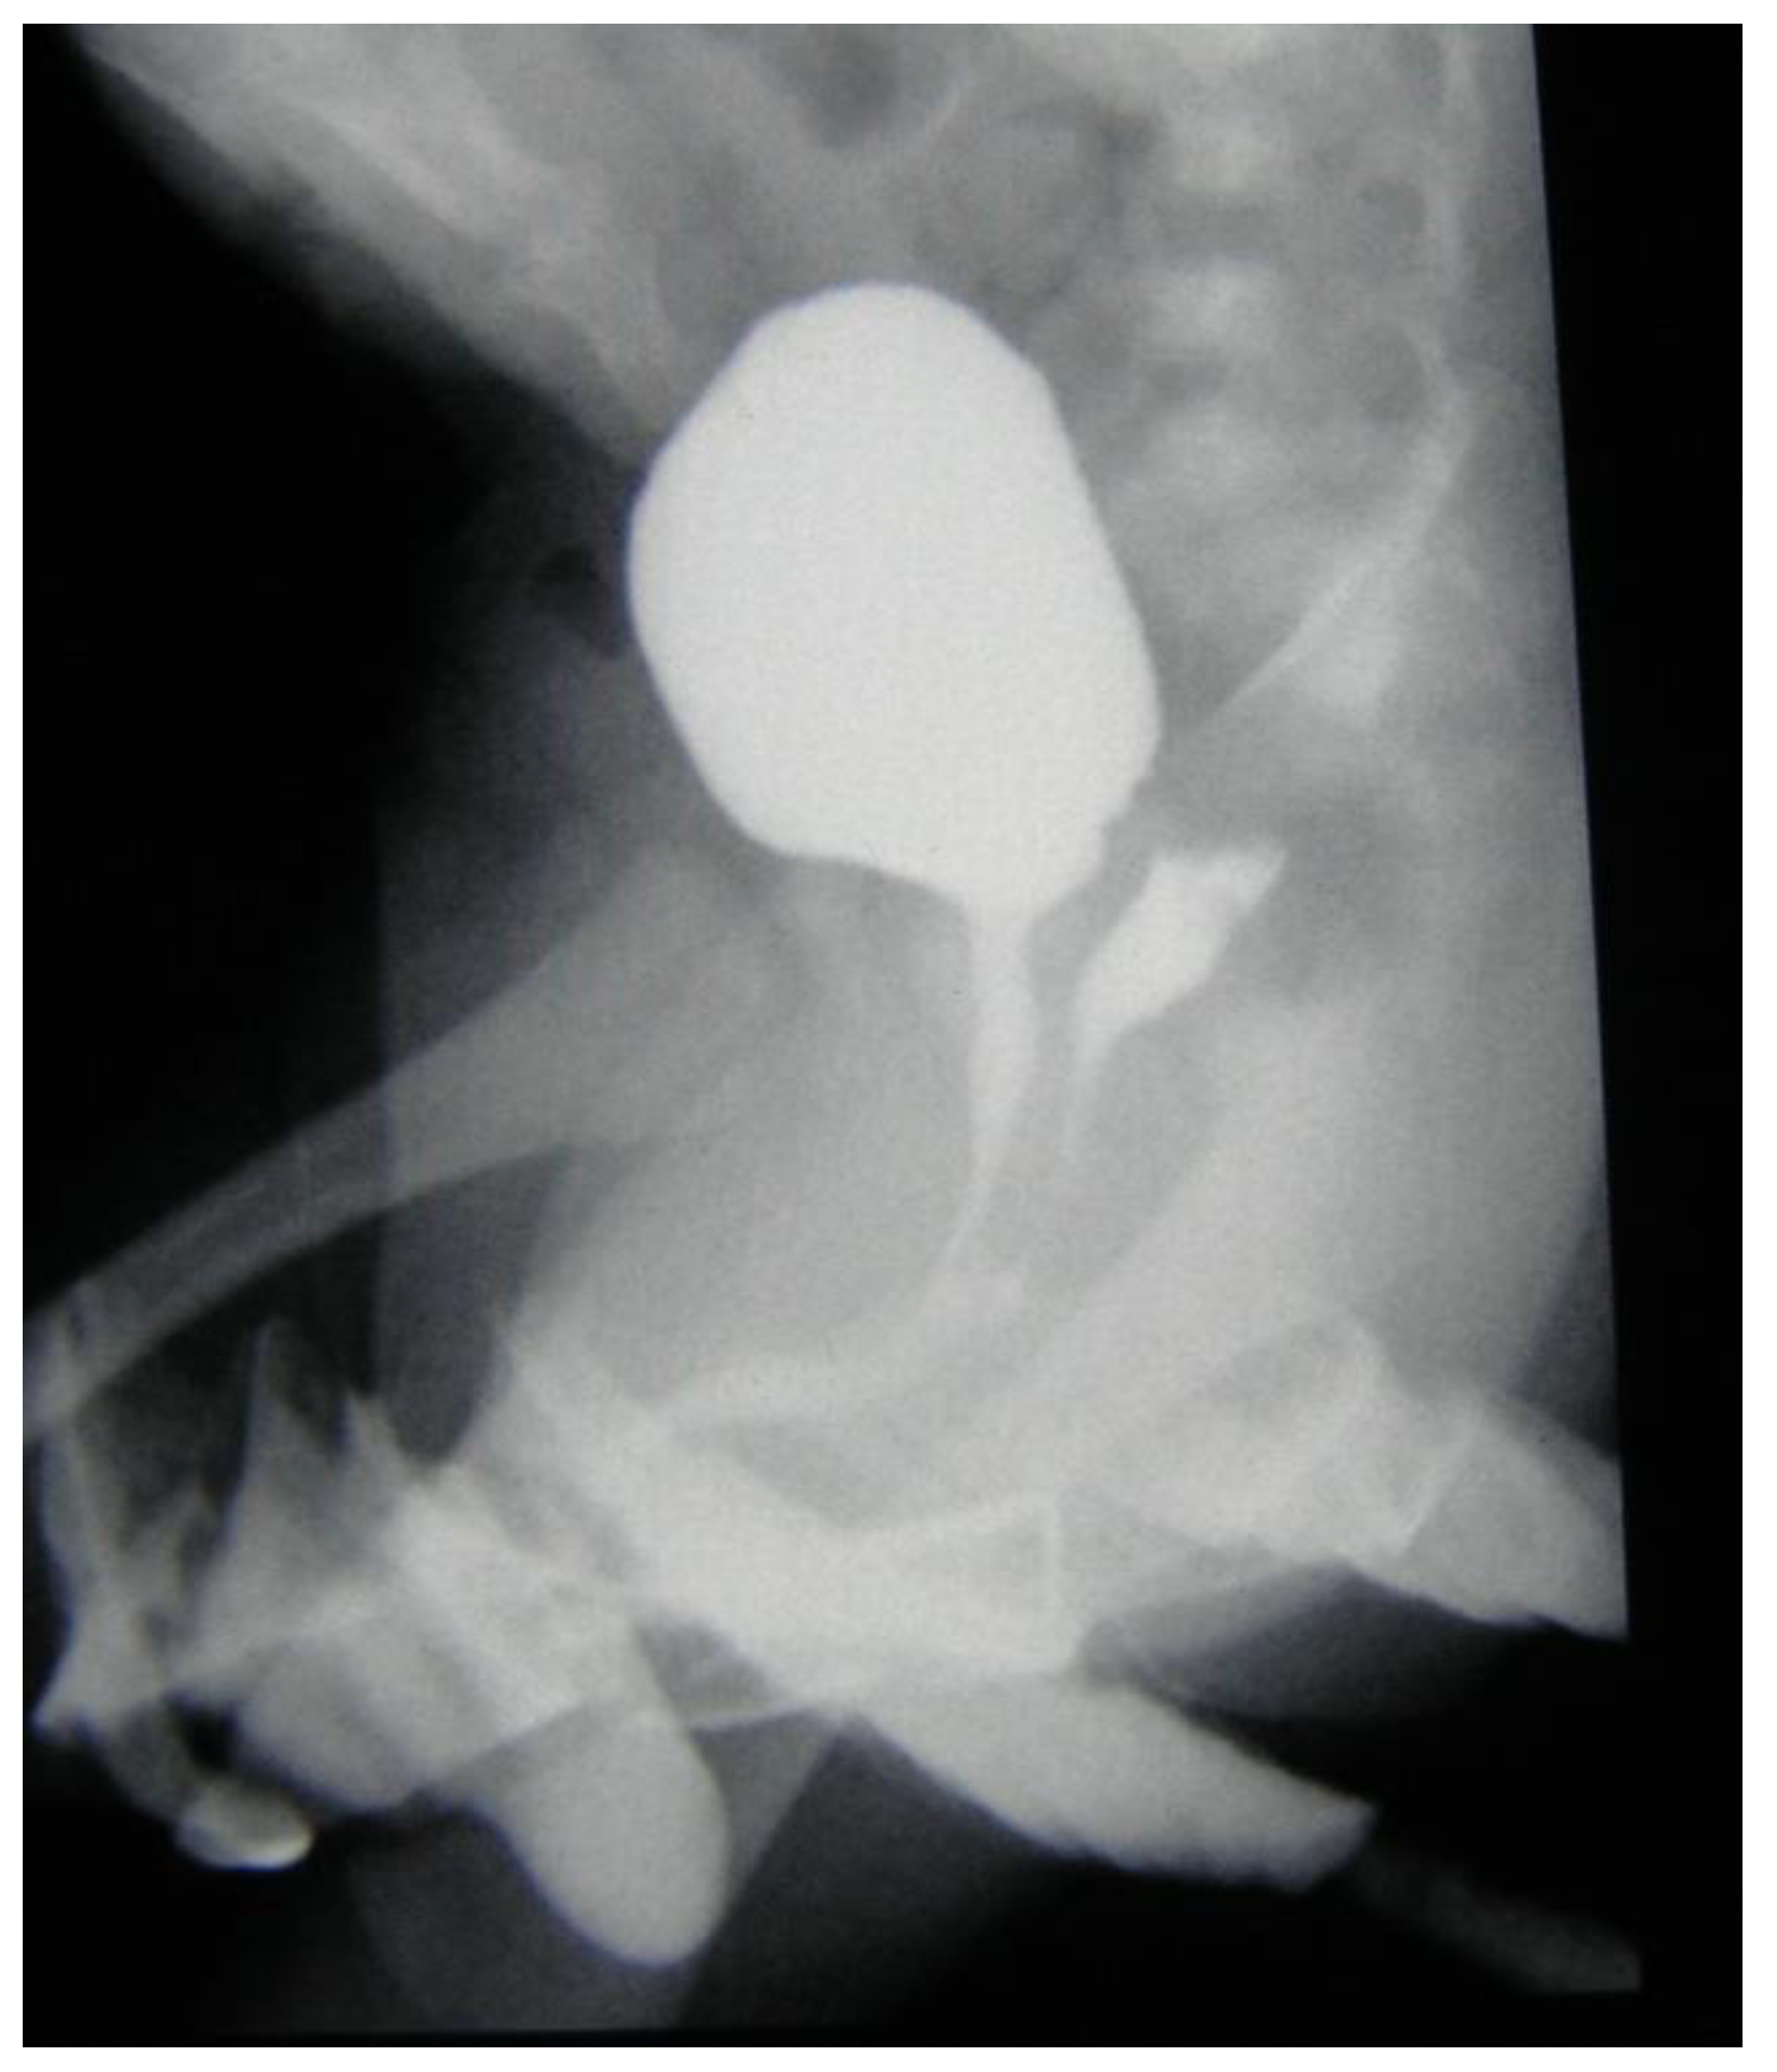

2.2. Surgical Procedures